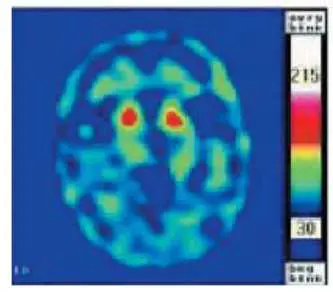

附圖為 99mTc-TRODAT-1 腦 SPECT 橫斷面(轉換為熱色彩偽彩圖),可見雙側基底核區域有兩個明顯的高攝取熱點(紅/橙色區域),呈對稱分佈,整體形態完整飽滿,符合「逗號形」的正常或接近正常紋狀體攝取型態。這樣的影像表現意味著 DAT 功能尚存,代表攝取降低型失智(如巴金森氏病失智症、DLB)並不符合——但本題考點在於:若附圖呈現的是攝取減少(如僅剩尾狀核,或出現不對稱的卵圓形殘影),則最符合巴金森氏病失智症(Parkinson's dementia)的表現。

考題設計邏輯:題目呈現一張 DAT-SPECT 影像,並詢問哪種失智症最可能出現「附圖的影像」。結合選項,答案 D(巴金森氏病失智症)符合 DAT-SPE